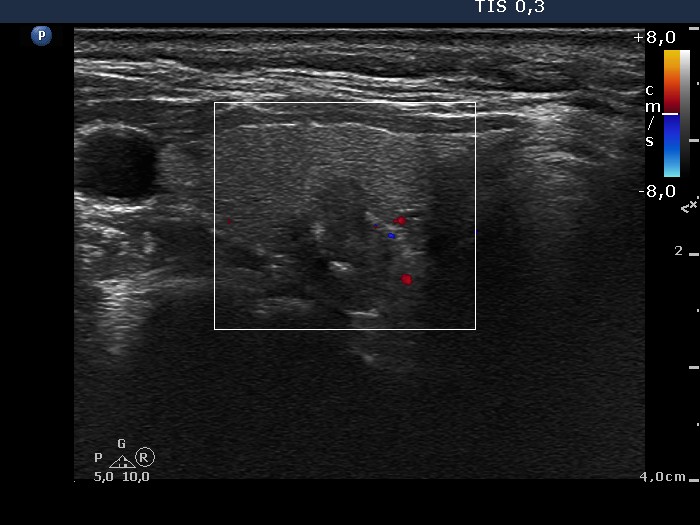

Ultrasonography. The thyroid was echonormal. There was a hypoechogenic lesion in the dorsal part of the right lobe. The nodule presented microcalcifications and hyperechogenic patches. No vascularization could be detected.